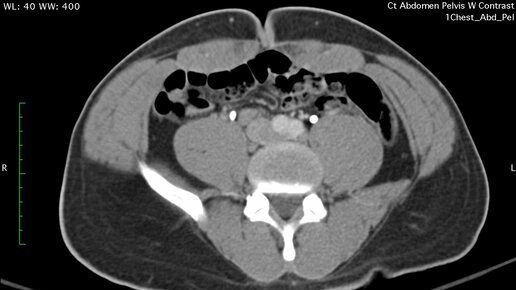

Что покажет КТ брюшной полости и КТ малого таза (видео)